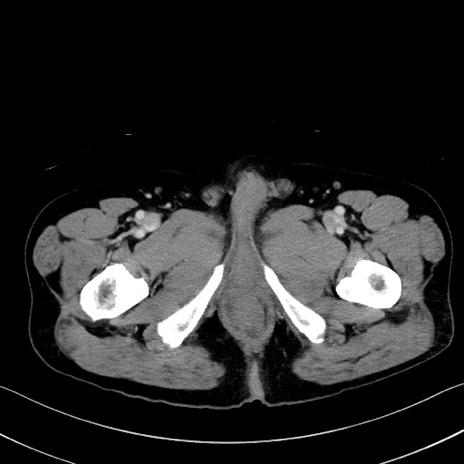

症例35(横断像)

【症例】70歳代 男性

【主訴】腹部膨満、嘔吐

【現病歴】昨日より腹部膨満感出現。本日増悪し、仙痛出現。嘔吐あり、受診。

【既往歴】糖尿病、胆摘後

【身体所見】BP 149/80mmHg、HR 74/min、BT 35.9℃、腹部:膨満、軟、圧痛なし。腸雑音減弱あり。上腹部正中切開瘢痕あり。

【データ】WBC 13500、CRP 1.72